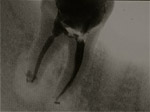

Traitement endodontique d’une 3ème molaire inférieure. Calcul de la longueur des racines.

Obturation du système endodontique à la gutta après désinfection.

Anatomie canalaire complexe et courbure apicale traitées.